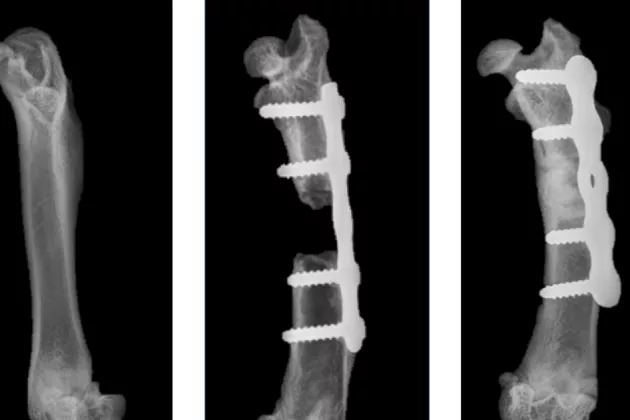

Bones in the human body have a fantastic ability to repair injury, but some defects are so large or complicated that the healing process is delayed or absent. This may be due to the bone having been subjected to a major trauma in connection with a traffic accident for example, or a tumour or infection causing a major bone defect. These cases are currently treated through bone transplantation, usually with bone taken from the patient’s own pelvis.

“In cases involving severe open fractures in the lower leg, over 5 per cent of all fractures fail to heal. With our method, we will be able to avoid taking bone from the pelvis, which is a major gain for the patient.”

“The bone protein we use has had negative effects in previous studies due to a secondary premature bone resorption, among other things. We have successfully mitigated this effect with the bisphosphonate and, by packaging the drug in a slowly resorbing bone substitute, we can control the speed of release. In the current study with the combination, we achieved a six-fold reduction in the amount of protein compared to previous efforts, while still inducing bone formation. The result was that even fractures with an extensive bone defect could heal without complications. We believe this finding will be of great clinical use in the future”, says Deepak Raina.